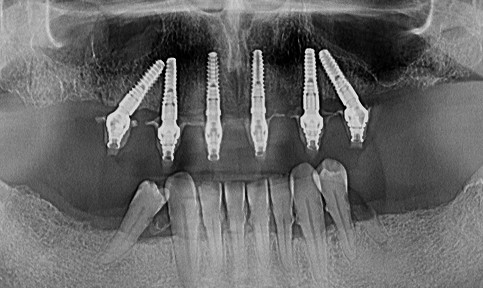

Tratamentul cu dinți ficși în 24 de ore constă în utilizarea implanturilor dentare pentru a reda o dantură completă într-un timp foarte scurt.

De cele mai multe ori, procedura implică inserarea a 4 sau 6 implanturi, PE CARE SE VA ANCORA O LUCRARE FIXĂ, asigurând înlocuirea tuturor dinților lipsă într-o singură zi.

Constă în realizarea unei radiografii 3D (CBCT) pentru o analiză detaliată a volumului osos si densității osoase.

Tot această metodă ne permite sa planificăm digital planul de tratament, adica să pozitionăm in puncte strategice a implanturilor.

Aceasta este etapa în care inserăm implanturile dentare. Procedura durează, în general, între 2 și 3 ore pe arcadă, în funcție de numărul de implanturi necesare și complexitatea cazului.

Ce tip de implanturi folosim pentru dantura fixă într-o zi?

Implantul dentar clasic

Implantul dentar zigomatic

Implanturile de tip zigomatic sunt concepute pentru situațiile cu deficit major de țesut osos la nivelul maxilarului superior, unde inserarea unor implanturi convenționale devine imposibilă. Acestea se ancorează în osul zigomatic, având lungimi mari, de regulă între 35 și 55 mm, pentru a asigura o stabilitate corespunzătoare în condiții extreme.